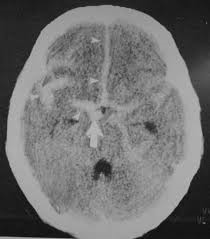

Beynimiz jelatin kıvamında bir dokudur ve beyin omurilik sıvısının içinde adeta yüzmektedir. Bu sıvı ayrıca beynin derininde yer alan ventrikül adı verilen boşlukları doldurmaktadır. Böylece beyin sarsıntıdan etkilenmez ve beyin omurilik sıvısı içinde batmaz bir şekilde yüzmektedir.

Beyin omurilik sıvısı ventriküller boyunca birbiriyle bağlantı yapan kanallar sayesinde devirdaim yapmaktadır.

Beyin omurilik sıvısının üretim, akım ve emilim süreci arasındaki varolan hassas denge, sıvının kafa içerisinde normal basınç altında devirdaim yapabilmesi açısından çok önemlidir. İşte hidrosefali denilen klinik tablo bu hassas dengenin bozulması durumunda ortaya çıkar. Örneğin ventriküller arasında geçişi sağlayan kanalların daralması veya sıvının emilmesinde bir hasar olması gibi sıvının devirdaimi sürecinde herhangi bir basamakta aksama olması hidrosefali oluşumuna neden olmaktadır.

Beyin omurilik sıvısının emilimindeki defekt normal basınçlı hidrosefaliye neden olmaktadır, çoğunluklada yaşlı populasyonda görülmektedir. Normal basınçlı hidrosefalide fazla miktardaki sıvı ventriküllerde genişlemeye neden olmaktayken beyin dokusu üzerinde bir basınç artışına sebep olmaz. Bu klinik tablo herhangi bir yaralanma yada başka bir hastalık sebebiyle oluşabilmekteysede çoğu vakada herhangi bir neden saptanamaz.

Doktorunuz semptom ve bulguları değerlendirdiğinde hidrosefaliden şüphelenirse tanıyı koymadan önce ayrıntılı bir şekilde hastalığın gidişatını öğrenmeli, ayrıntılı bir fiziksel ve nörolojik inceleme yapmalı, CT veya MRG ile görüntüleme yapmalıdır. Tetkikler sonucunda hidrosefali teşhisi konursa hasta daha ileri tetkik ve tedavi için beyin cerrahi uzmanına refere edilmeli.